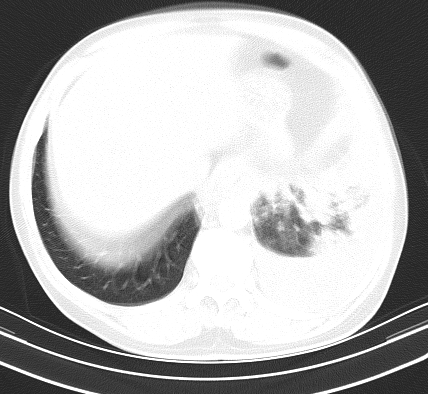

以下是引用老爱克斯新网客在2008-7-31 6:30:00的发言:[br]左肺上叶大片状病灶,左肺上叶支气管狭窄呈鼠尾状,左肺门增大,纵隔内见肿大淋巴结,左侧胸腔积液,余肺清晰。左肺中心型肺癌淋巴结转移,

以下是引用zjb在2008-7-31 6:32:00的发言:[br]左侧中心性肺癌 阻塞性肺炎 肺不张 胸腔积液 建议气管镜

以下是引用zjzjr在2008-7-31 8:45:00的发言:[br]考虑左侧中心性肺癌伴阻塞性肺炎,左肺上叶肺不张,纵隔淋巴结转移;左侧胸腔积液。建议行纤支镜检查。

以下是引用sdzyy在2008-7-31 8:47:00的发言:[br]病灶较治疗前有所进展,胸水增多, 左侧中心性肺癌 并 阻塞性肺炎 肺不张 胸腔积液 可能性大; 建议气管镜检查。 [br] [br]